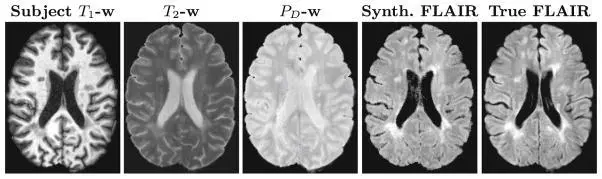

PSICLONE (Pulse Sequence Information-based Contrast Learning On Neighborhood Ensembles) is an image synthesis and intensity standardization framework.

PSICLONE estimates approximate pulse sequence parameters of a given MR image to generate subject-specific training images that are used to train a random forest regression to synthesize a target contrast. The learnt regression is applied to the given image to generate a synthetic or a standardized image.

REPLICA (Regression Ensembles with Patch Learning for Image Contrast Agreement) is a supervised, multi-resolution image synthesis approach that uses random forests as the main regression engine. REPLICA can be used as an image synthesis approach on its own as well as a subroutine in PSICLONE.